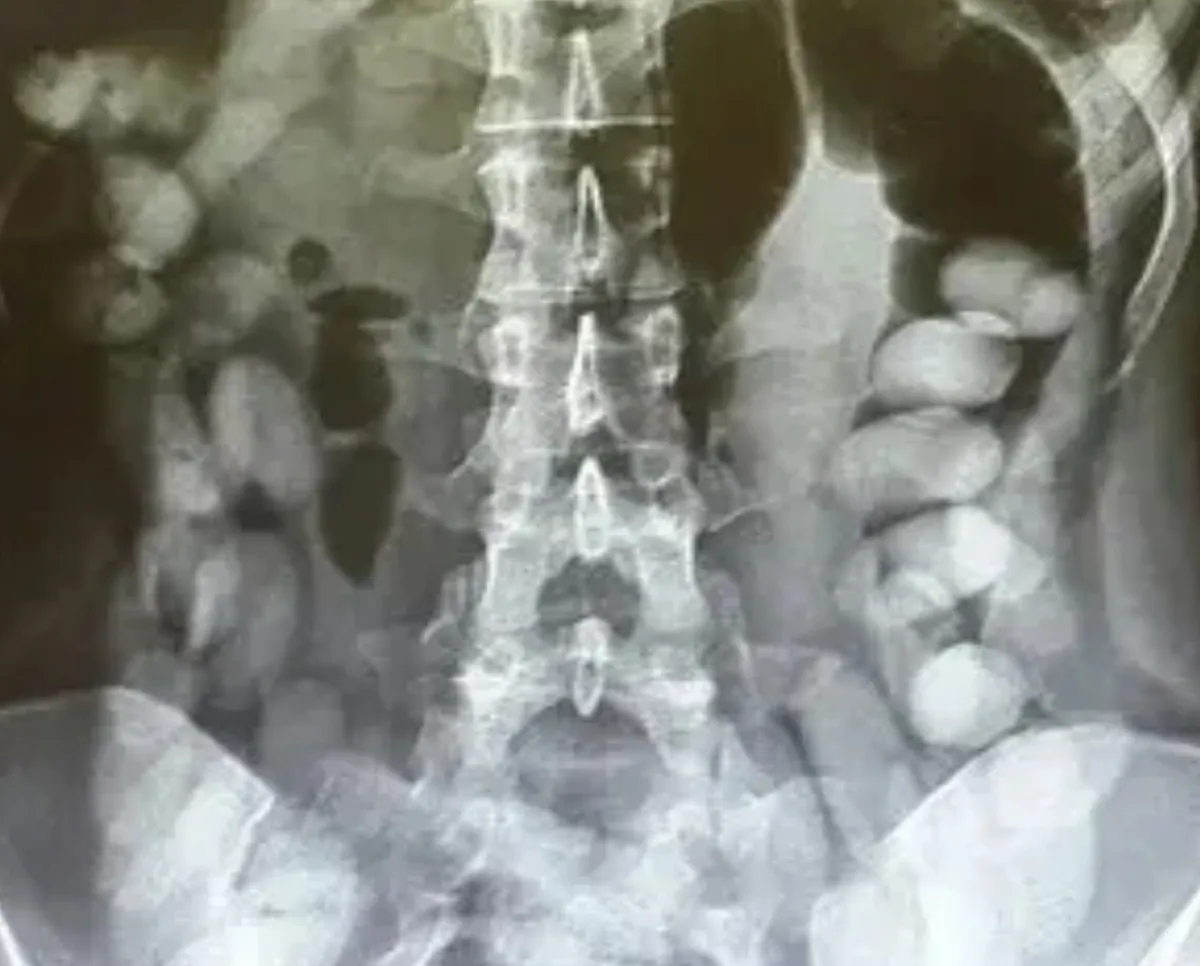

مخاطب۲۴- کاشانی رئیس بیمارستان شهید محمدی بندرعباس با اعلام خبر خروج بیش از ۱۰۰ بسته مواد مخدر جاسازی شده از بدن یک جوان ۲۲ ساله اظهار کرد: این جوان در تاریخ ۱۴۰۳/۱۰/۷ در شهر حاجی آباد تصادف کرده و به مرکز درمانی حاجی آباد منتقل شد که به دنبال بررسیهای مختلف درمانی مشخص میشود که فرد حامل پکهای مواد مخدر در شکمش بوده است.

روانبخش مدیر تیم اتاق عمل نیز در این رابطه گفت: تیم اتاق عمل در طول شب در حال جراحی و خارج کردن پکهای مواد مخدر بودند که تعدادی بالغ بر ۱۰۰ پک به وزن کلی بیش از یک کیلوگرم از بدن بیمار خارج شد که تحویل مقام حراست بیمارستان و مقامات انتظامی داده شد.